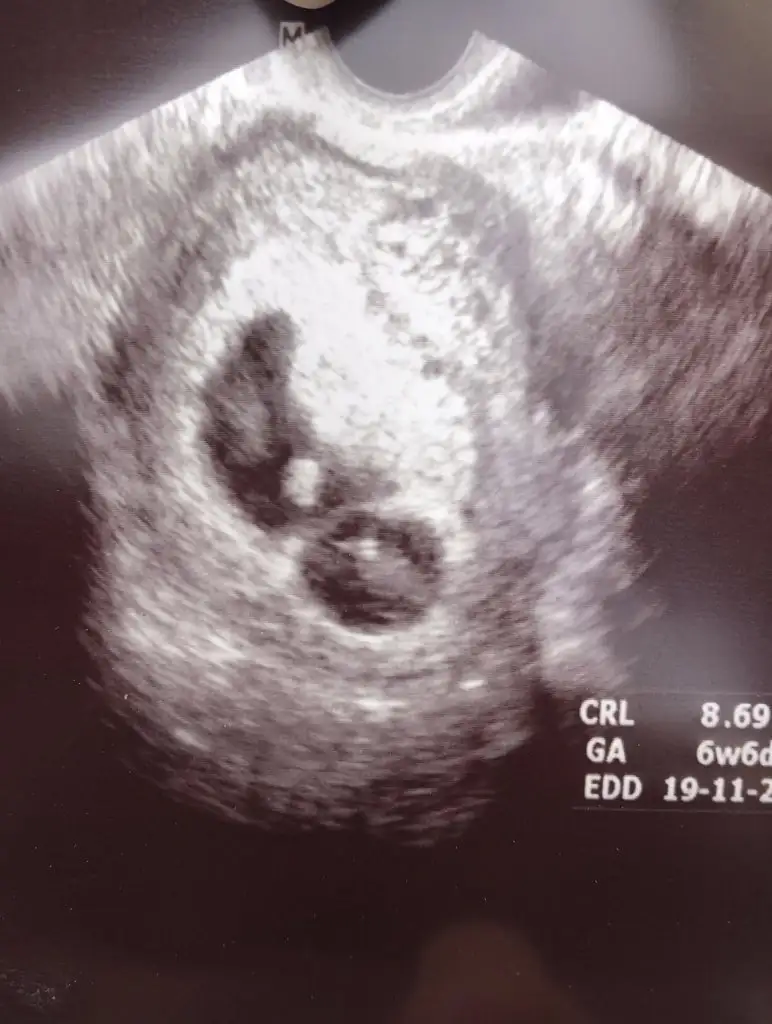

6+2 vajinal ultrasonSelam Kızlarbir çok kişi gruplardan beni bilir. Yine yetiştim imdatlara

5 ve 14. haftaya kadar olan ultrason fotolarınızı paylaşın. Vajinadan mı yoksa karından mı çekildiğini ve kaç haftalık olduğunu da mutlaka belirtin.

kuzu yolk sac büyük sende yer değişebilir şuan tahmin etmeyim sen bir sonraki foton olunca onu paylaş6+2 vajinal ultrason